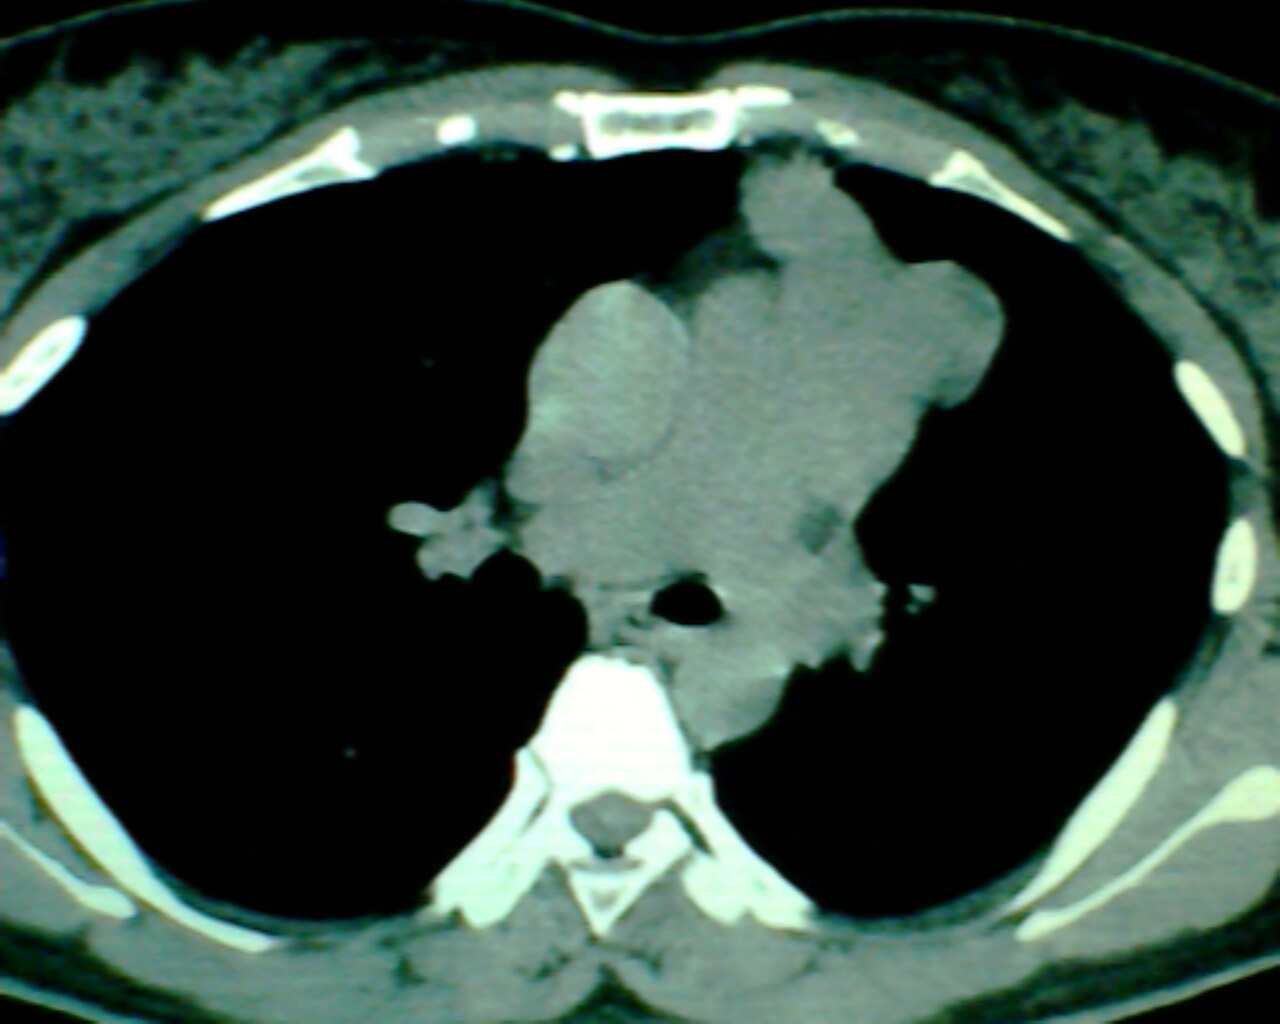

以下是引用狙击手在2007-4-10 22:46:00的发言:[br]考虑:左上纵膈旁型肺癌。理由:1,肿块与纵隔间有分隔;2,肿块呈分叶状;3,肿块突出面圆心在肺内;4,纵隔左移;5,纵隔内器官未见受压征象。